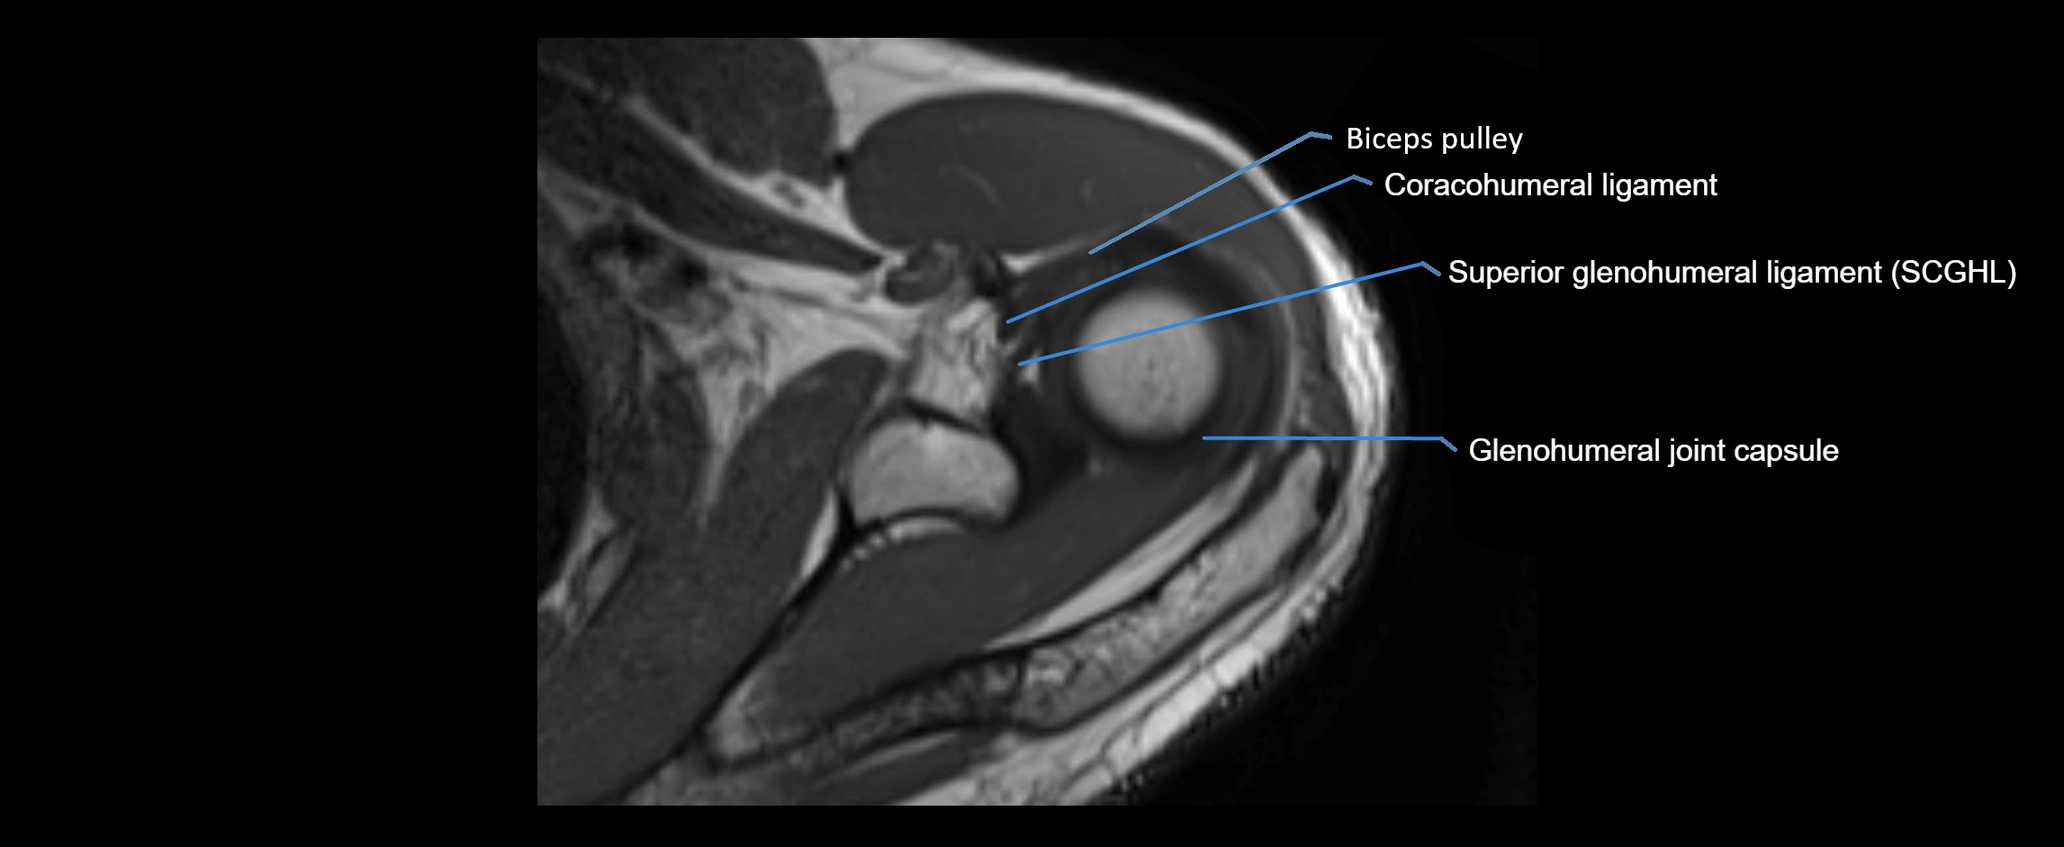

MRI images

image